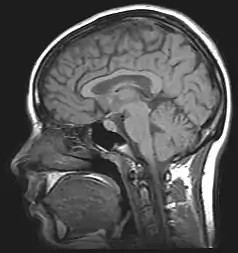

| For the diagnosis, brain scans (such as MRI) should be done to rule out other potential causes | |

Neuroimaging, usually with computed tomography (CT/CAT) or magnetic resonance imaging (MRI), is used to exclude any mass lesions. In IIH these scans typically appear to be normal, although small or slit-like ventricles, dilatation and buckling[17] of the optic nerve sheaths and "empty sella sign" (flattening of the pituitary gland due to increased pressure) and enlargement of Meckel's caves may be seen.

An MR venogram is also performed in most cases to exclude the possibility of venous sinus stenosis/obstruction or cerebral venous sinus thrombosis.[5][7][8] A contrast-enhanced MRV (ATECO) scan has a high detection rate for abnormal transverse sinus stenoses.[14] These stenoses can be more adequately identified and assessed with catheter cerebral venography and manometry.[15] Buckling of the bilateral optic nerves with increased perineural fluid is also often noted on MRI imaging.